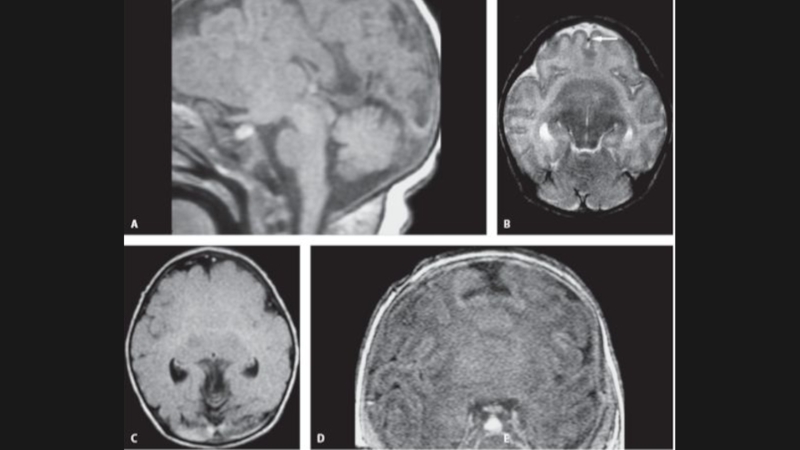

Слайд 38Мальформация Dandy-Walker

Данная мальформация представляет собой кистозное расширение IV желудочка,

сочетающееся с агенезией червя мозжечка, высоким расположением мозжечкового

намета и гидроцефалией

“Классическая” МДУ:

-кистозная дилатация IV желудочка - увеличенная ЗЧЯ;

-гипоплазия червя мозжечка, его краниальная ротация;

Гипоплазия червя мозжечка c ротацией(ГЧР):

-непостоянная гипоплазия червя мозжечка,

-ЗЧЯ/ствол мозга нормальных размеров,

-киста небольшая или отсутствует;

Персистирующая киста кармана Блейка(ККБ):

-сообщение “открытого” IV желудочка с кистой;

Мега цистерна магна(МЦМ):

-увеличенные околомозжечковые цистерны сообщаются с базальными субарахноидальными пространствами.

Мальформация Dandy-WalkerДанная мальформация представляет собой кистозное расширение IV желудочка,   сочетающееся с агенезией червя мозжечка, высоким